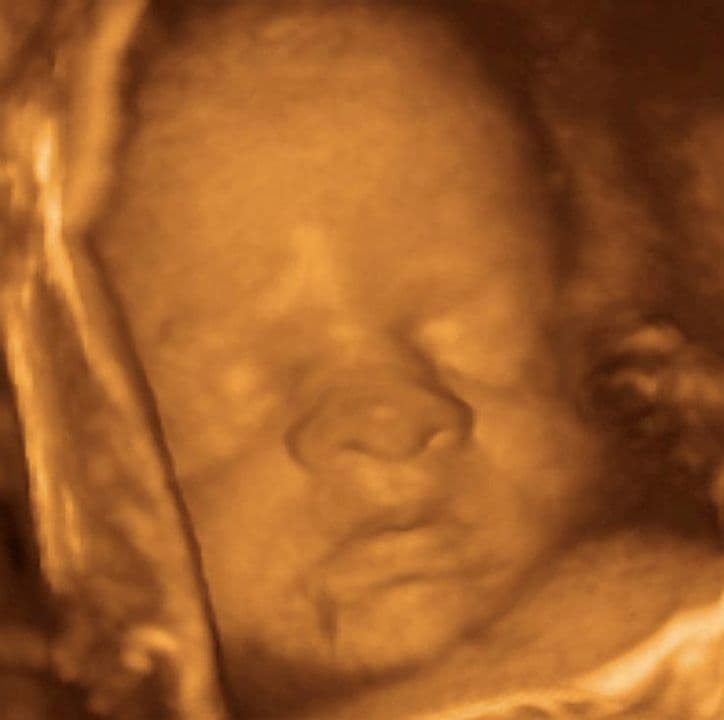

In this 3D scan the baby’s arm is held up next to the face. This type of scan shows external features but also looks inside the baby in 3D so you may see some parts of your baby “through” an arm or leg. Here, the baby’s ear can be seen through the arm.